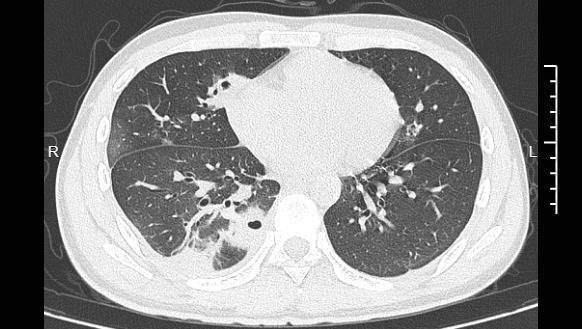

熬到第三天,小林已经烧到39℃,赶紧来到宁波大学附属第一医院就诊。接诊的丁群力主任医师一看他的症状,立刻安排了CT检查。结果显示:小林的肺里有十几个空洞,部分肺组织已经坏死拿柜配资,这是典型的血源性肺脓肿。

小林的CT影像显示肺里有多个空洞